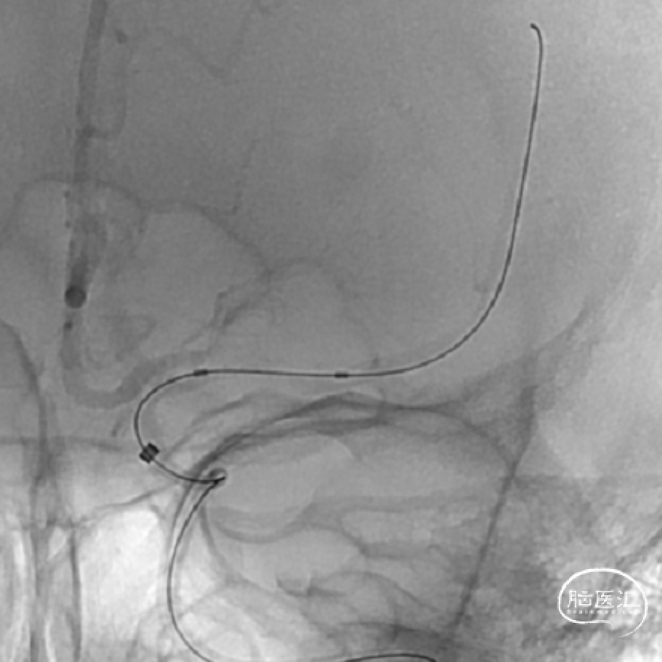

手术过程

1、左侧颈内动脉造影

2、Synchro微导丝过病变

微导丝过病变

调整微导丝选择较粗、较平直的分支动脉。

SL-10微导管造影

3、Gateway球囊扩张

4、Neuroform® EZ定位释放

沿微导丝送入XT-27微导管,经微导管送入3.5mm*15mm Neuroform® EZ至狭窄处,定位后释放。